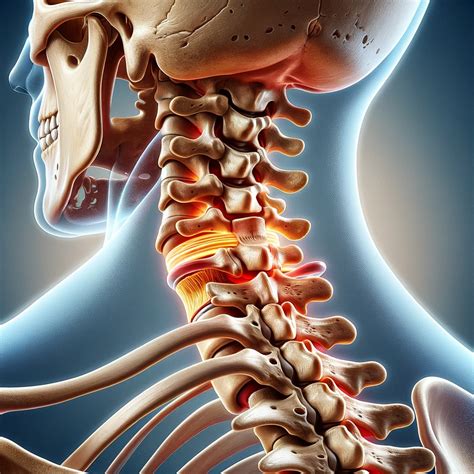

A bulging disc in the neck is a common spinal condition that can cause significant discomfort and pain. The cervical spine, which consists of seven vertebrae in the neck, supports the head and allows for a range of motion. Each vertebra is separated by a disc that acts as a shock absorber and provides flexibility. When a disc bulges, it can press on nearby nerves, leading to various symptoms.

The symptoms of a bulging disc in the neck can vary depending on the severity and location of the bulge. Common symptoms include:

• Neck pain: Persistent or intermittent pain in the neck, which may worsen with certain movements.

• Radiating pain: Pain that radiates from the neck to the shoulders, arms, or hands.

• Numbness or tingling: Sensations of numbness or tingling in the arms, hands, or fingers.

• Weakness: Weakness in the arms or hands, which may affect grip strength or the ability to perform fine motor tasks.